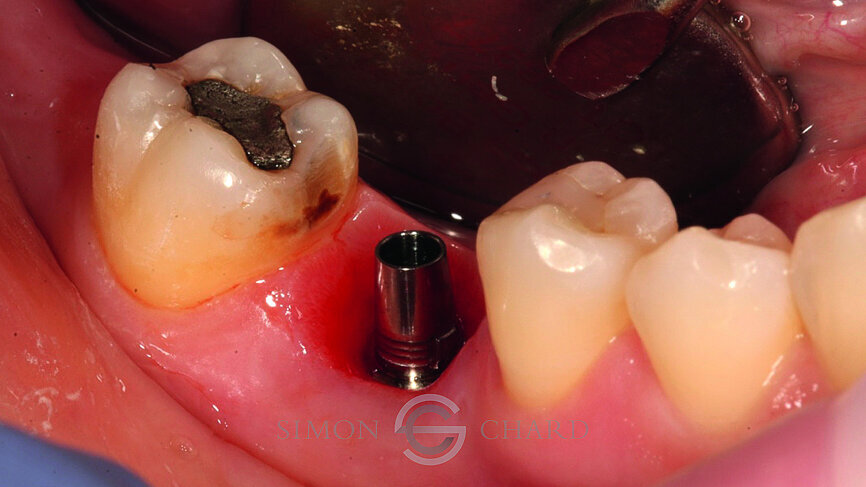

Following 3 months of integration, the patient attended the practice for the restoration of the implant with a definitive crown. During this period, the soft tissue had been given time to mature and a beautiful molar soft tissue profile had formed (Figs. 4 & 5).

Traditionally, capturing the detail of this soft tissue profile with analogue methods is complicated and time consuming; however, utilising a digital intraoral scan (CEREC Omnicam) a “gingival mask scan” can be taken to accurately replicate this soft tissue and use it to guide the subgingival emergence profile of the restoration (Fig. 6).

Following removal of the temporary crown, a TiBase was placed into the fixture head and a scan body used as a reference point for the scanning of the implant (Figs. 7 & 8).